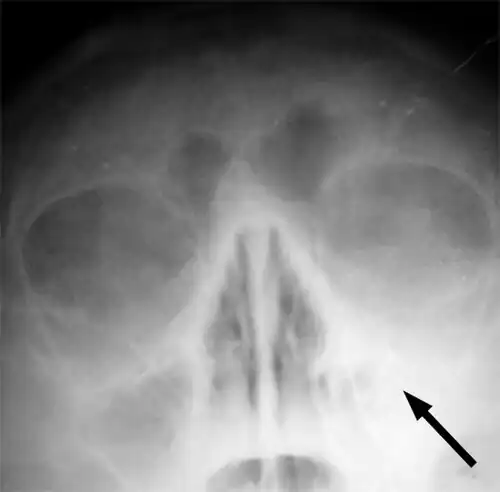

-

X-ray of left-sided maxillary sinusitis marked by an arrow. There is a lack of air transparency, indicating fluid in contrast to the other side.

Imaging by either X-ray, CT, or MRI is generally not recommended unless complications develop.[66] Pain caused by sinusitis is sometimes confused for pain caused by pulpitis (toothache) of the maxillary teeth, and vice versa. Classically, the increased pain when tilting the head forwards separates sinusitis from pulpitis.[68]